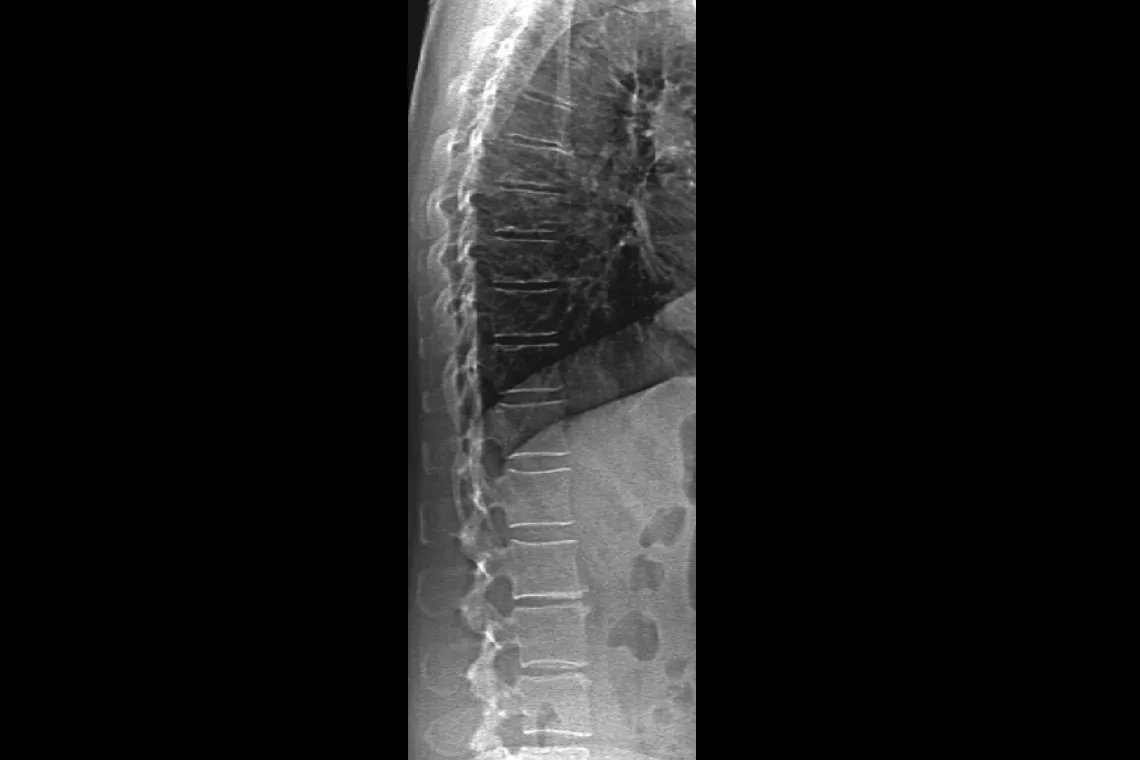

Visualise calcified plaque in the abdominal aorta, which may be a significant indication of heart disease and stroke, two of the leading causes of death in men and women.

Assess fracture risk by combining an accurate measurement of bone density with high-resolution vertebral imaging. You can identify spine fractures with a low-dose, single-energy image in 10 seconds.